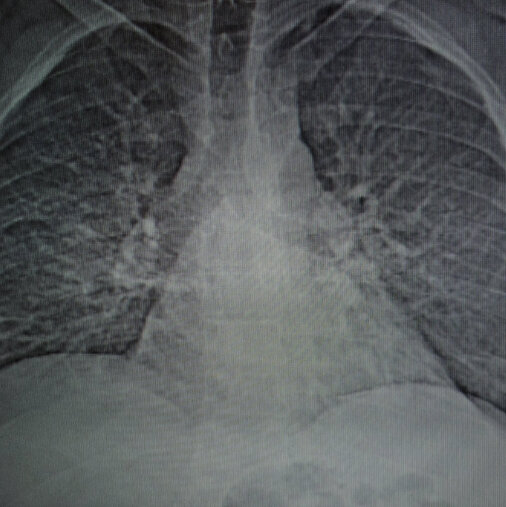

The Federal Coal Mine Health and Safety Act of 1969 allows disabled miners who have been diagnosed with coal workers pneumoconiosis also known as black lung disease to collect monthly compensation and medical benefits. Real-time Threat Protection Password Manager Firewall for PC or Mobile More. Norton Community Hospital Phone Directory.

280 Virginia Ave NE. The purpose of the Black Lung Clinics Program is to reduce the morbidity and mortality associated with occupationally-related coal mine dust lung disease through the provision of quality medical outreach educational and benefits counseling services for active inactive retired and disabled US coal miners. DISTRICT 5 VA Norton Virginia 276 679-0230 DISTRICT 6 EASTERN KY Pikeville Kentucky 606 432-0944.

This is a public health crisis of major magnitude says Joseph Wolfe an attorney in Norton Va who represents miners filing for government black lung benefits. Its a chronic disease common among those who breathe in coal dust in the mines of Southwest Virginia. Vishal Raj MD is a Geriatric Medicine Specialist in Norton VA.

Unfortunately black lung plagues many coal miners in our region. 8 Sheridan Square Suite 310. Community Home Care 276 439-1460.